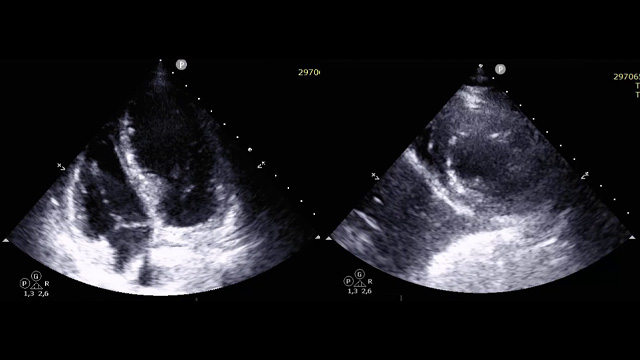

Severe MR in a high-risk patient with a suboptimal anatomy for M-TEER: what other options can we find?

Multimodality imaging reveals fibro-calcific leaflet disease, restricted motion, and a short posterior leaflet, making him a suboptimal candidate for M-TEER and prompting consideration of transcatheter mitral valve replacement. How would you treat?